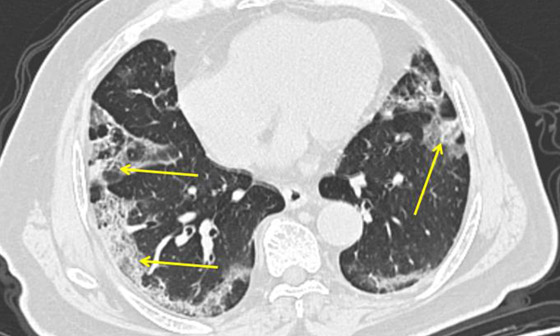

تصوير مقطعي محوسب من مستشفى جامعة جورج واشنطن يُظهر آثار فيروس كورونا المستجد، أو ما يُعرف بـ"كوفيد-19" رئتي رجل عمره 59 عاماً. فشاهدوا معنا في الفيديو المدهش أدناه كيف تبدو رئة مصاب بفيروس كورونا (فيروس كوفيد 19) وما يحصل داخلها..